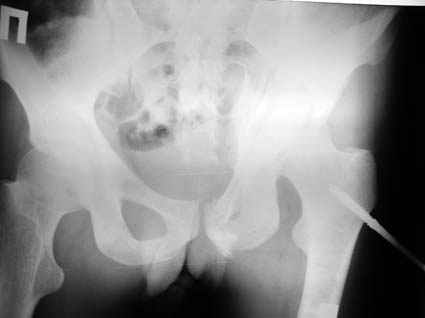

Все-таки надо бы начать не с КТ, а с обзорного снимка таза и косых проекций впадины.

Это обзорные и косые снимки

С уважением,

Leonid

Привет, Леонид. Оскольчатый высокий двухколонный перелом в такие сроки трогать не надо, т.к. это про такие переломы сказано: "кто с ножом на Ж. пойдет тот в ней и останется...".